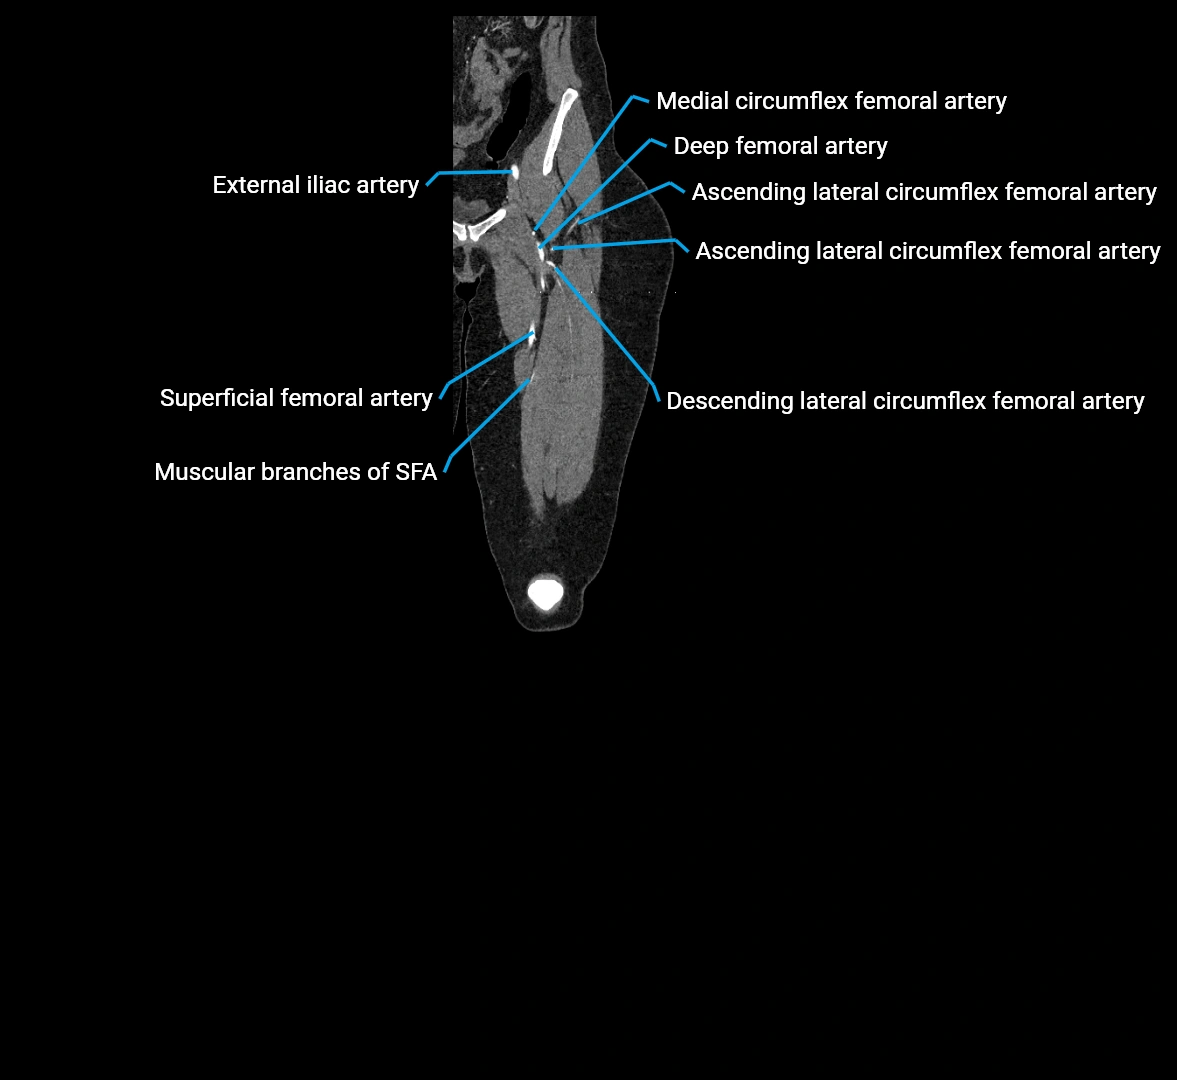

CT images

image